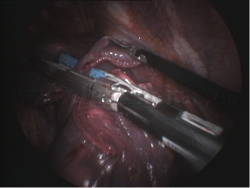

Exéresis de nódulos y metástasis